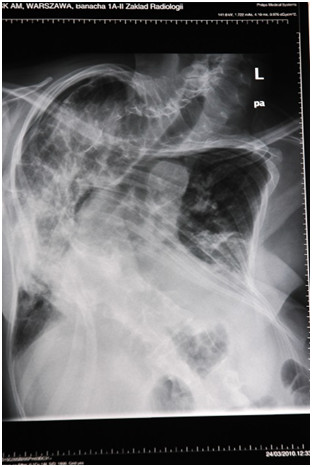

36-letni pacjent zgłosił się do poradni penumonologicznej z powodu duszności, narastającego od kilku miesięcy zmęczenia i duszności wysiłkowej po wejściu na 3 piętro. W badaniu fizykalnym stwierdzono cichy szmer pęcherzykowy z bardzo dyskretnymi trzeszczeniami. W badaniach dodatkowych spirometria: FEV1/FVC 0,76; FEV1 3,85 [L] (85%N, 9,1 percentyl), VC 5,24 [L] (91%N, 16 percentyl), TLC 7,18 [L] (74,5%N i 2,6 percentyl); TLCO SB 7,28 [mmol/L/min/kPa] (58%N 0,2 percentyl). Wykonano HRCT oraz bronchofiberoskopię z BAL - uzyskano mleczny wygląd popłuczyn oraz + barwienie PAS. Obraz HRCT przedstawiono na skanie poniżej. Metodą leczenia z wyboru będzie: